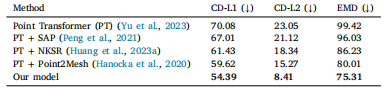

Table 2Comparison of our model with the sate of the art methods in the domain. Metrics arethe same as in Table 1.

表2:我们的模型与该领域最先进方法的比较。所使用的评估指标与表1中的相同。

Table 5Comparative analysis of mesh Reconstruction methods. Metrics are the same as inTable 4.

表5:网格重建方法的对比分析。所使用的评估指标与表4中的相同。